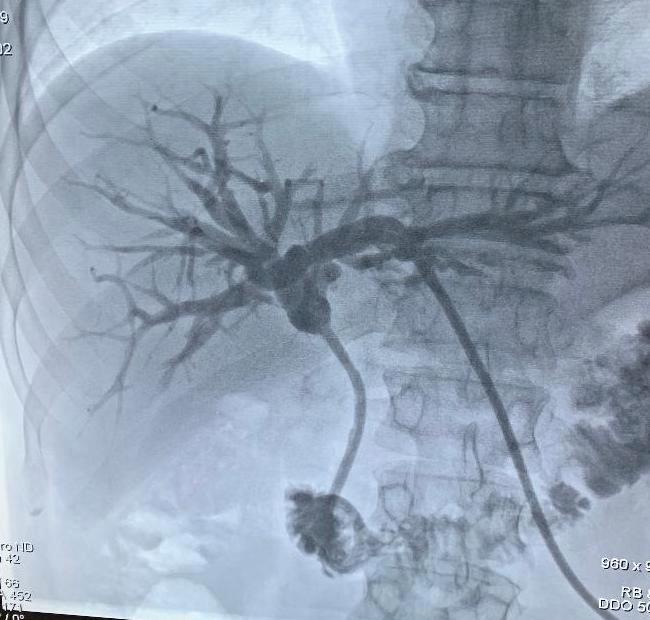

INTERVENCIONAL

Patología pelviana femenina y manejo intervencional. Dr. Nicolás Martínez

Manejo malformaciones vasculares. Dr. Gian Paolo Zamboni

Manejo estenosis biliares. Dr. Nicolás Zugbe

Acceso endoscópico biliar percutáneo. Dr. Marcos Tapia

Técnicas de Ablacíon (Desde la alcoholización a la electroporación). Dr. Marcelo Klein

Coffee Break: Exhibición comercial y pósters

Ablación del cuello más allá del bocio. Dr. José Luis del Cura

Equipo Pert Dr. Diego González

Trombectomía mecánica en el tromboembolimo pulmonar. Dr. Marcos Tapia

Ablación percutánea cáncer de pulmón. Dr. Eduardo Eyheremendy

Principios diagnóstico y tratamiento fístulas de diálisis. Dr. Eduardo Eyheremendy

Manejo endovascular del TEP, revisión de la evidencia. Dr. David Clemo